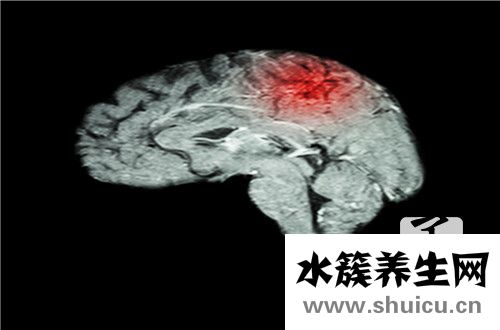

人腦是人體最重要的器官,屬于中樞神經系統的高級部分。 關鍵是左腦和右腦。 左右半球的職責是不同的。 對大腦和神經的理解有益于我們進行更有力的鍛煉,尤其是在孩子的成長不完全時,關鍵的發展設計...